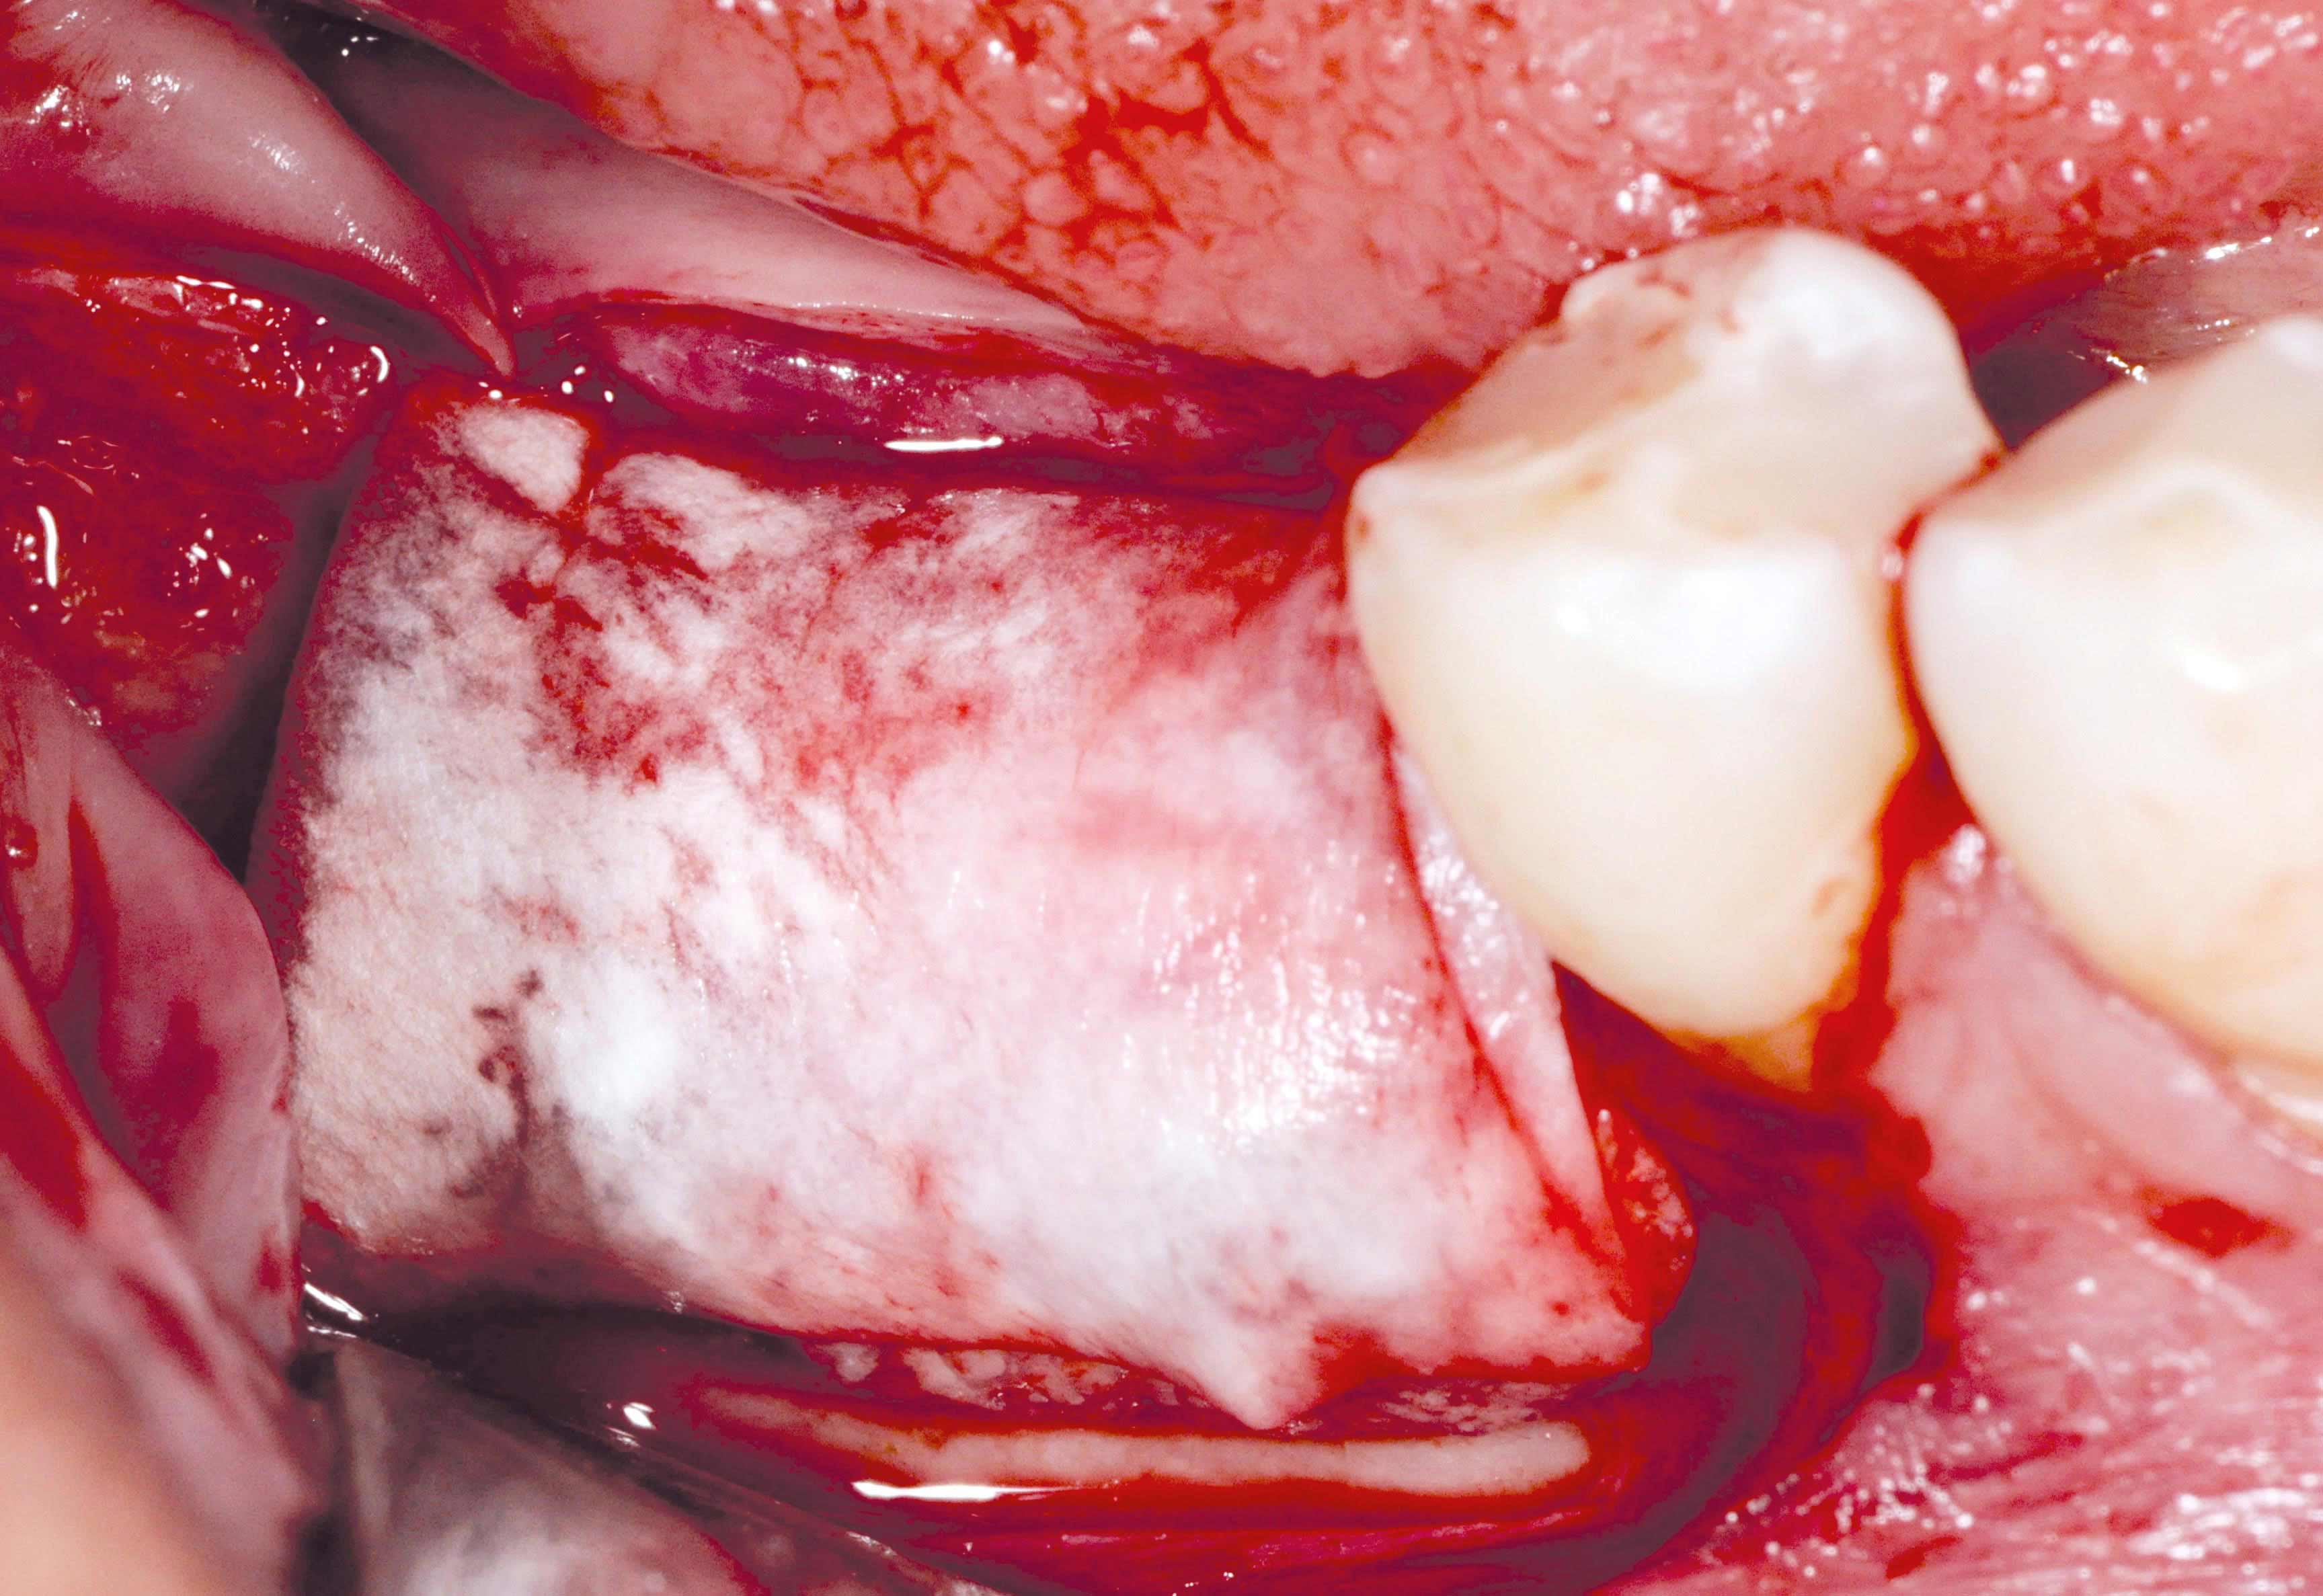

botiss maxgraft® bonebuilder and vestibuloplasty with mucoderm® for ridge augmentation - Clinical case